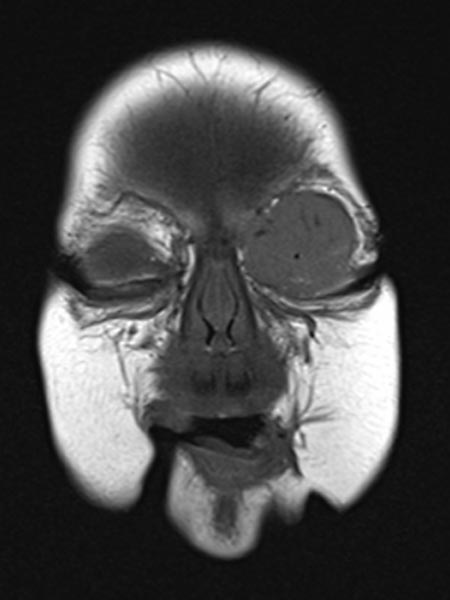

Coronal plane of T1-weighted MRI without contrast shows the mass homogeneously hypointense. Centrally, a few small flow voids visible, caused by strongly perfused arterial vessels.